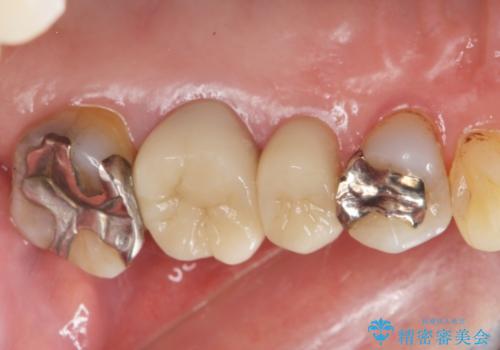

70代女性 段差のある被せ物のやり替え

- 左下の大臼歯(6番)の根の治療を行いました。

その代わり、現在ある歯をしっかり治療することになり、左上下の治療を行っています。

左上56間が狭かったため、写真にはないですが、セパレーションを2回ほど行い、歯根間距離を広げてから処置を行っています。

そのまま無理やり歯型を取って製作するよりも、ご自身で清掃ができる形態にできるため、長期的な予後が期待できます。